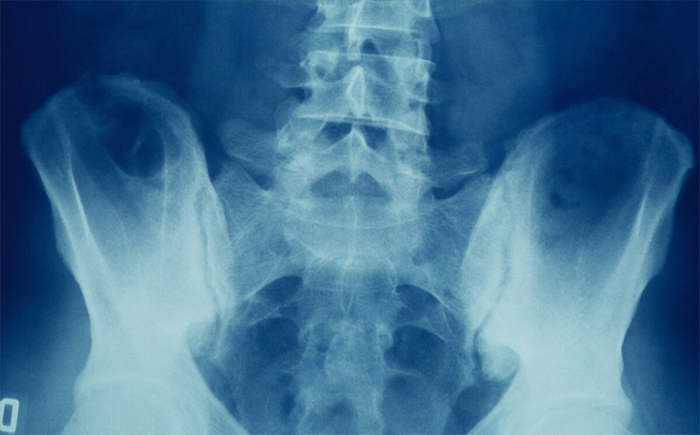

强直性脊柱炎导致的腰疼一般持续时间较久,基本上大于等于三个月,且越是休息疼痛感越强。尤其是下腰部位置,自骶部由下而上开始出现疼痛,并且这些部位活动受限,下蹲困难,高度怀疑是强直性脊柱炎,可以去医院通过常规X线片、CT、MRI检查与体格检查等来诊断。